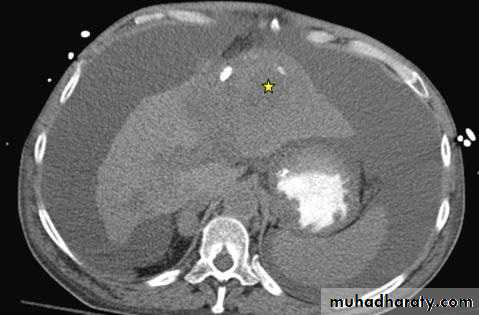

B- Radiologic features; includes U/S of abdomen with or without Doppler of the portal and hepatic venous vessels. CT or MRI; which show liver atrophy with nodular surface and features of portal hypertension.

CT image of upper abdomen revealing cirrhotic liver with a large mass in left hepatic lobe (star) and massive ascites

Cross-section of liver showing green-yellow hepatocellular carcinoma in left hepatic lobe (star).